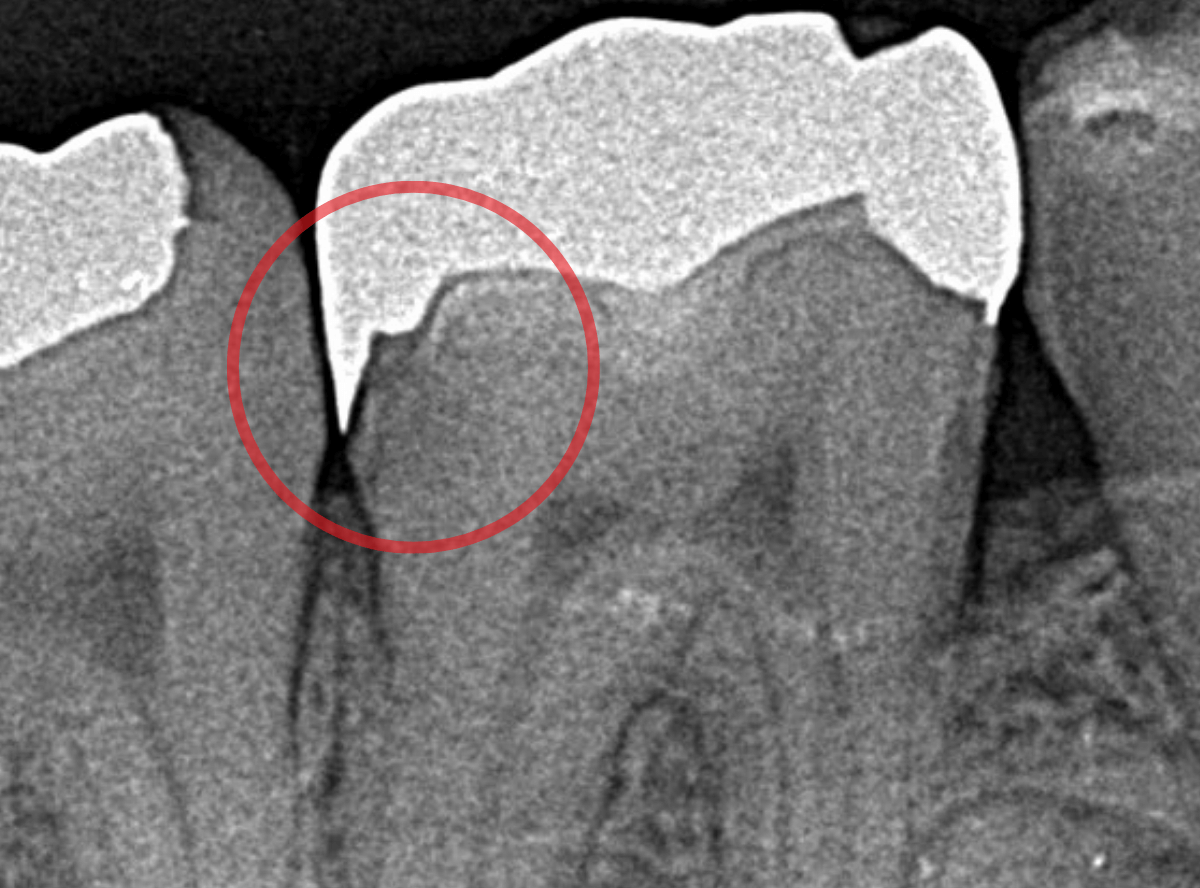

今回は、深い虫歯が進行してしまったさし歯をセラミックで治療し直したケースを動画でご紹介します。

検査をすると、さし歯の周りの歯肉から出血が多いため、レントゲン写真で確認すると、さし歯の中で虫歯が進行していると診断されました。

神経を取っているさし歯の中の虫歯は、レントゲン写真でも正確にはわからず痛みもないため、さし歯をはずしてみないと、どれくらい進行しているかははっきりわかりません。

虫歯と診断されたさし歯の中は一体どうなっているのでしょうか?